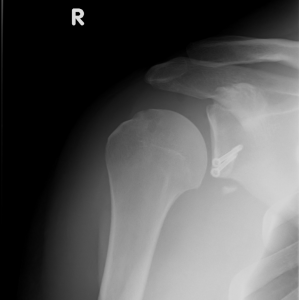

Zustand nach Vergrößerung der Gelenkspfanne mittels patienteneigenem Knochentransfer aus dem Rabenfortsatz und dessen Verschraubung am vorderen Pfannenrand.